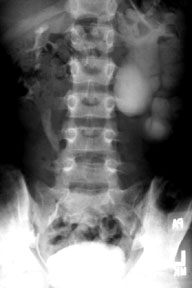

Intravenous Pyelogram (IVP) Showing Hydronephrosis

This film shows the abdomen 20 minutes after contrast was injected intravenously. Concentration of the contrast is seen in both kidneys. The right kidney and ureter are seen to be normal. Notice the rather delicate cup-like white structures caudal to the right 12th rib. These are the calyces of the right kidney. The left kidney has hydronephrosis. Notice the large, round white areas to the right of the lumbar vertebra. This is the pelvis (large medial collection of contrast) and calyces (smaller lateral white to light gray circles) of the left kidney. They are dilated because there is an obstruction at the ureteropelvic junction. The ureter is never seen.